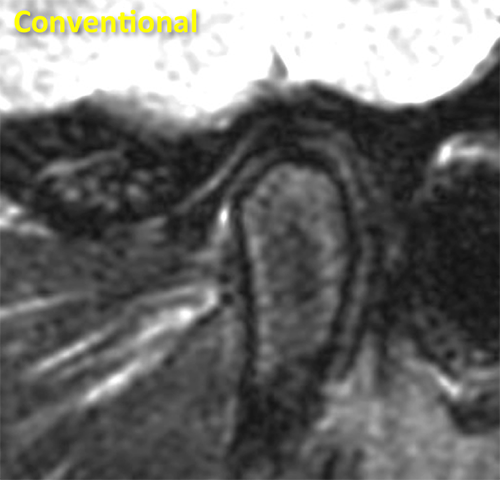

TMJ Conventional

Conventional sagittal fluid sensitive sequence of the TMJ shows the low signal intensity disc and the mandibular condyle.